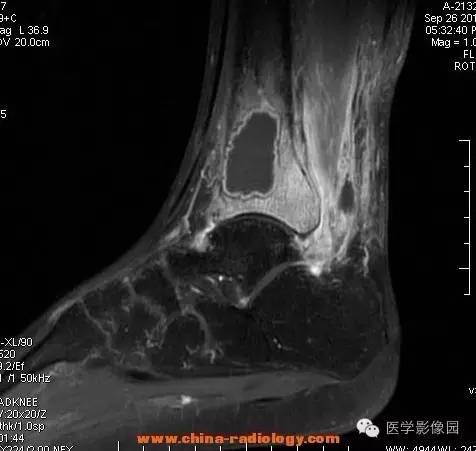

影像学表现:胫骨中下段干骺端不未规则形长T1长T2信号,T2WI见不完整环形稍低信号影,T2脂肪抑制低信号更明显,并见胫骨下段及踝关节后外侧软组织呈弥漫稍高信号,增强明显不均匀强化,增强见低信号环内有环形强化影。

影像学表现:表现为长骨干骺端有椭圆形密度减低区,边缘有清晰的骨质硬化,病变与邻近正常骨髓腔境界清楚。MRI上T1WI呈低信号,少数呈等信号,T2WI多为混杂高信号,增强扫描可见环状强化,强化的脓肿壁薄而均匀。